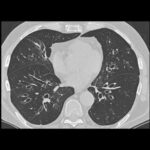

Para diagnosticar a bronquiectasia, o médico realiza o exame de ausculta pulmonar e pode detectar a presença de secreção em áreas específicas. Além disso, a tomografia computadorizada de tórax é um exame frequente para observar as áreas afetadas. Dependendo da extensão e dos sintomas, o tratamento pode ser clínico, com foco no controle das infecções, ou cirúrgico, em casos mais graves, como sangramento recorrente.